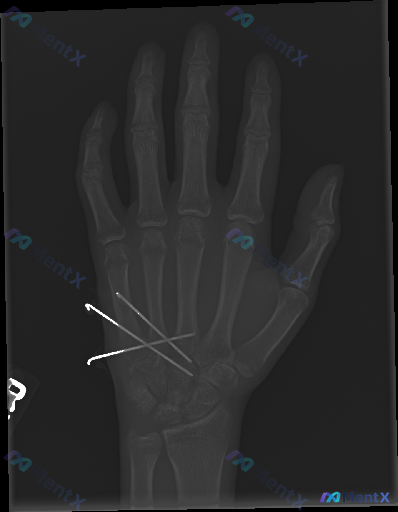

整理一份右手指部的X光正位影像资料,最醒目的是两枚金属克氏针——一枚从第3掌骨基底部穿到近节指骨,另一枚对应第4指,两根都跨了掌指关节,近端还在皮下留了钩状弯曲。 骨皮质能看到不连续或者陈旧性骨折线的痕迹,目前没看到明显的溶骨、广泛骨膜反应,植入物周围也没有透亮带。 问题来了:如果问“这张影像里有什...

各位同道好,今天带来一个右手外伤术后的X光病例讨论。 【简要病史】 右手多发掌骨基底部骨折术后复查(具体术后时间未提供)。 【影像描述】 - 骨骼:右手第2、3、4掌骨基底部可见交叉克氏针内固定影;对应部位骨皮质不连续,骨折线部分模糊,似见骨痂形成;其余掌指骨、腕骨未见明确骨折脱位或溶骨性破坏。 -...